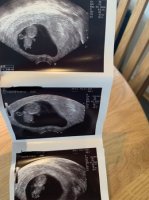

Ser jo ut som en liten bebi joVis vedlegget 303208 Alt fint på tul i dagTermin stemte meget godt med hva jeg hadde regnet ut selv, 10+6 i dag

Sammenliknet med uke 7. Nå gleder jeg meg masse til TUL nr 2 når jeg er 13 uker på vei!Ja. Ganske mye som skjer på kort tid. Forrige svangerskap var vi ca 1 uke tidligere. Så litt ut som en baby da også, men ikke like godt som denne gangenSer jo ut som en liten bebi joSammenliknet med uke 7. Nå gleder jeg meg masse til TUL nr 2 når jeg er 13 uker på vei!